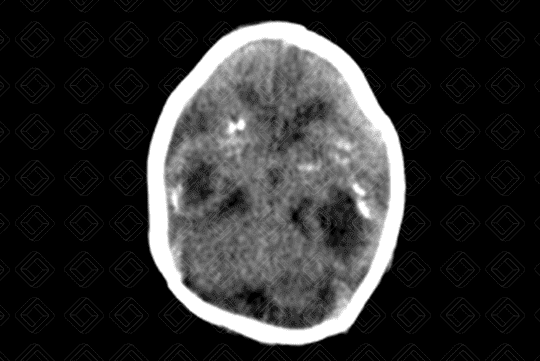

• Tomografia computadorizada do crânio evidenciando microcefalia, com importante atrofia cortical e dilatação compensatória do sistema ventricular;

• Observa-se a presença de calcificações de distribuição corticossubcortical (setas vermelhas) no parênquima encefálico e algumas menos evidentes, nos núcleos da base;